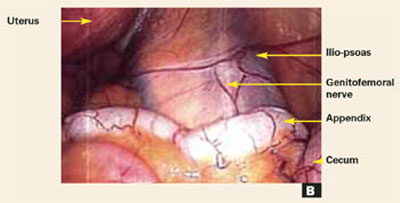

FIGURE 1B Inner concentric circle

Laparoscopic procedures. It may sometimes be appropriate to perform surgical therapy during a pelvic evaluation. For example, most ectopic pregnancies can be treated laparoscopically, as can many cases of endometriosis. It is desirable, however, to complete the pelvic examination before performing any subsequent procedures, including the removal of ovarian cysts, ovaries, fibroids, or the uterus, since blood and peritoneal trauma may make abnormal findings difficult to perceive.